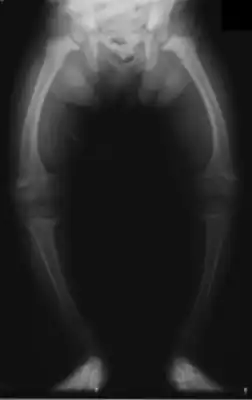

![]() Искривление нижних конечностей у двухлетнего ребёнка, страдающего рахитом. | |